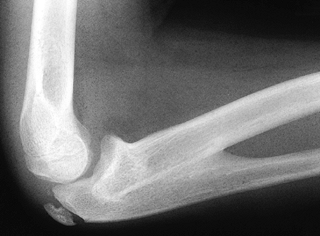

in posterior CDRH (see Fig. 165.27 and Fig. 165.28).

Elbow motion deficits are often minimal, usually nonprogressive, and

worse in anterior than posterior CDRH. Loss of supination is the most

prominent limitation in both anterior and posterior CDRH. Anterior CDRH

blocks full flexion, and posterior CDRH blocks full extension, causing

a flexion contracture (usually 30° or less). Wrist range of motion may

also be limited (1,9,97,111). In the infant, the unossified dislocated radial head may be visualized with diagnostic ultrasound (14), but the diagnosis is most commonly made by plain radiography (Fig. 165.27 and Fig. 165.28).

![]() |

|

Figure 165.28. AP and lateral views of a posterior dislocation of the radial head.